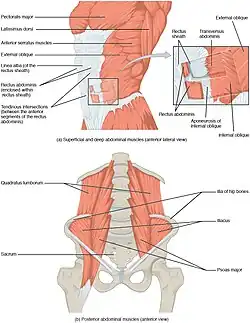

The top of the iliac crest includes the attachments of the latissimus dorsi, the transversus abdominis, as well as the internal and external obliques. The quadratus lumborum also connects from the back tip of the iliac crest up to the 12th rib.[18] These tendon and muscle structures surrounding the iliac crest are at risk for irritation due to iliocostal contact. Tendon irritation can result in referred pain, therefore affected individuals may experience pain throughout the hip, low back, the groin, chest, and thigh. This contributes towards the difficulty in diagnosis of iliocostal friction syndrome.[4]